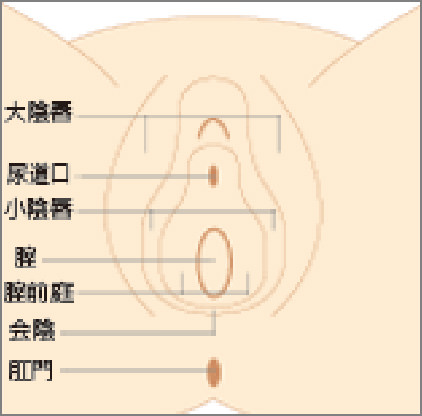

女性器について 正しい知識を持ちましょう ゆかりレディースクリニック 神戸市三宮にある婦人科

会陰 えいん は 腟口 ちつこう から肛門までを指します。 生殖器は発生学的由来により内生殖器と外生殖器に分けられます。外陰部は体表の皮膚が変化して生じた外生殖器で、外からの刺激に対して生殖器を守る役割があります。会陰部に近いほど男性化不全の程度が強い 4.陰嚢の形成は? 低形成、二分陰嚢の有無 <Quigley分類> 完全男性型 完全女性型 図:たのしく学ぶ小児内分泌より 外陰部の診察:女児の男性化 1.陰核の大きさは? 横径を計測することが多い。 >7 mm → 陰核肥大 2.膣口は確認できるか? 3.陰唇動画あり出張オイルリンパマッサージの四ツ目本舗は東京都心部のホテル・自宅へ、深夜1時迄、出張オイルリンパマッサージを提供。「no sokeibu, no life紙パンツを捨てよう!」当店の「鼠径部(そけい部)オイルリンパマッサージ」の「会陰部について」の説明

女性器について 正しい知識を持ちましょう ゆかりレディースクリニック 神戸市三宮にある婦人科